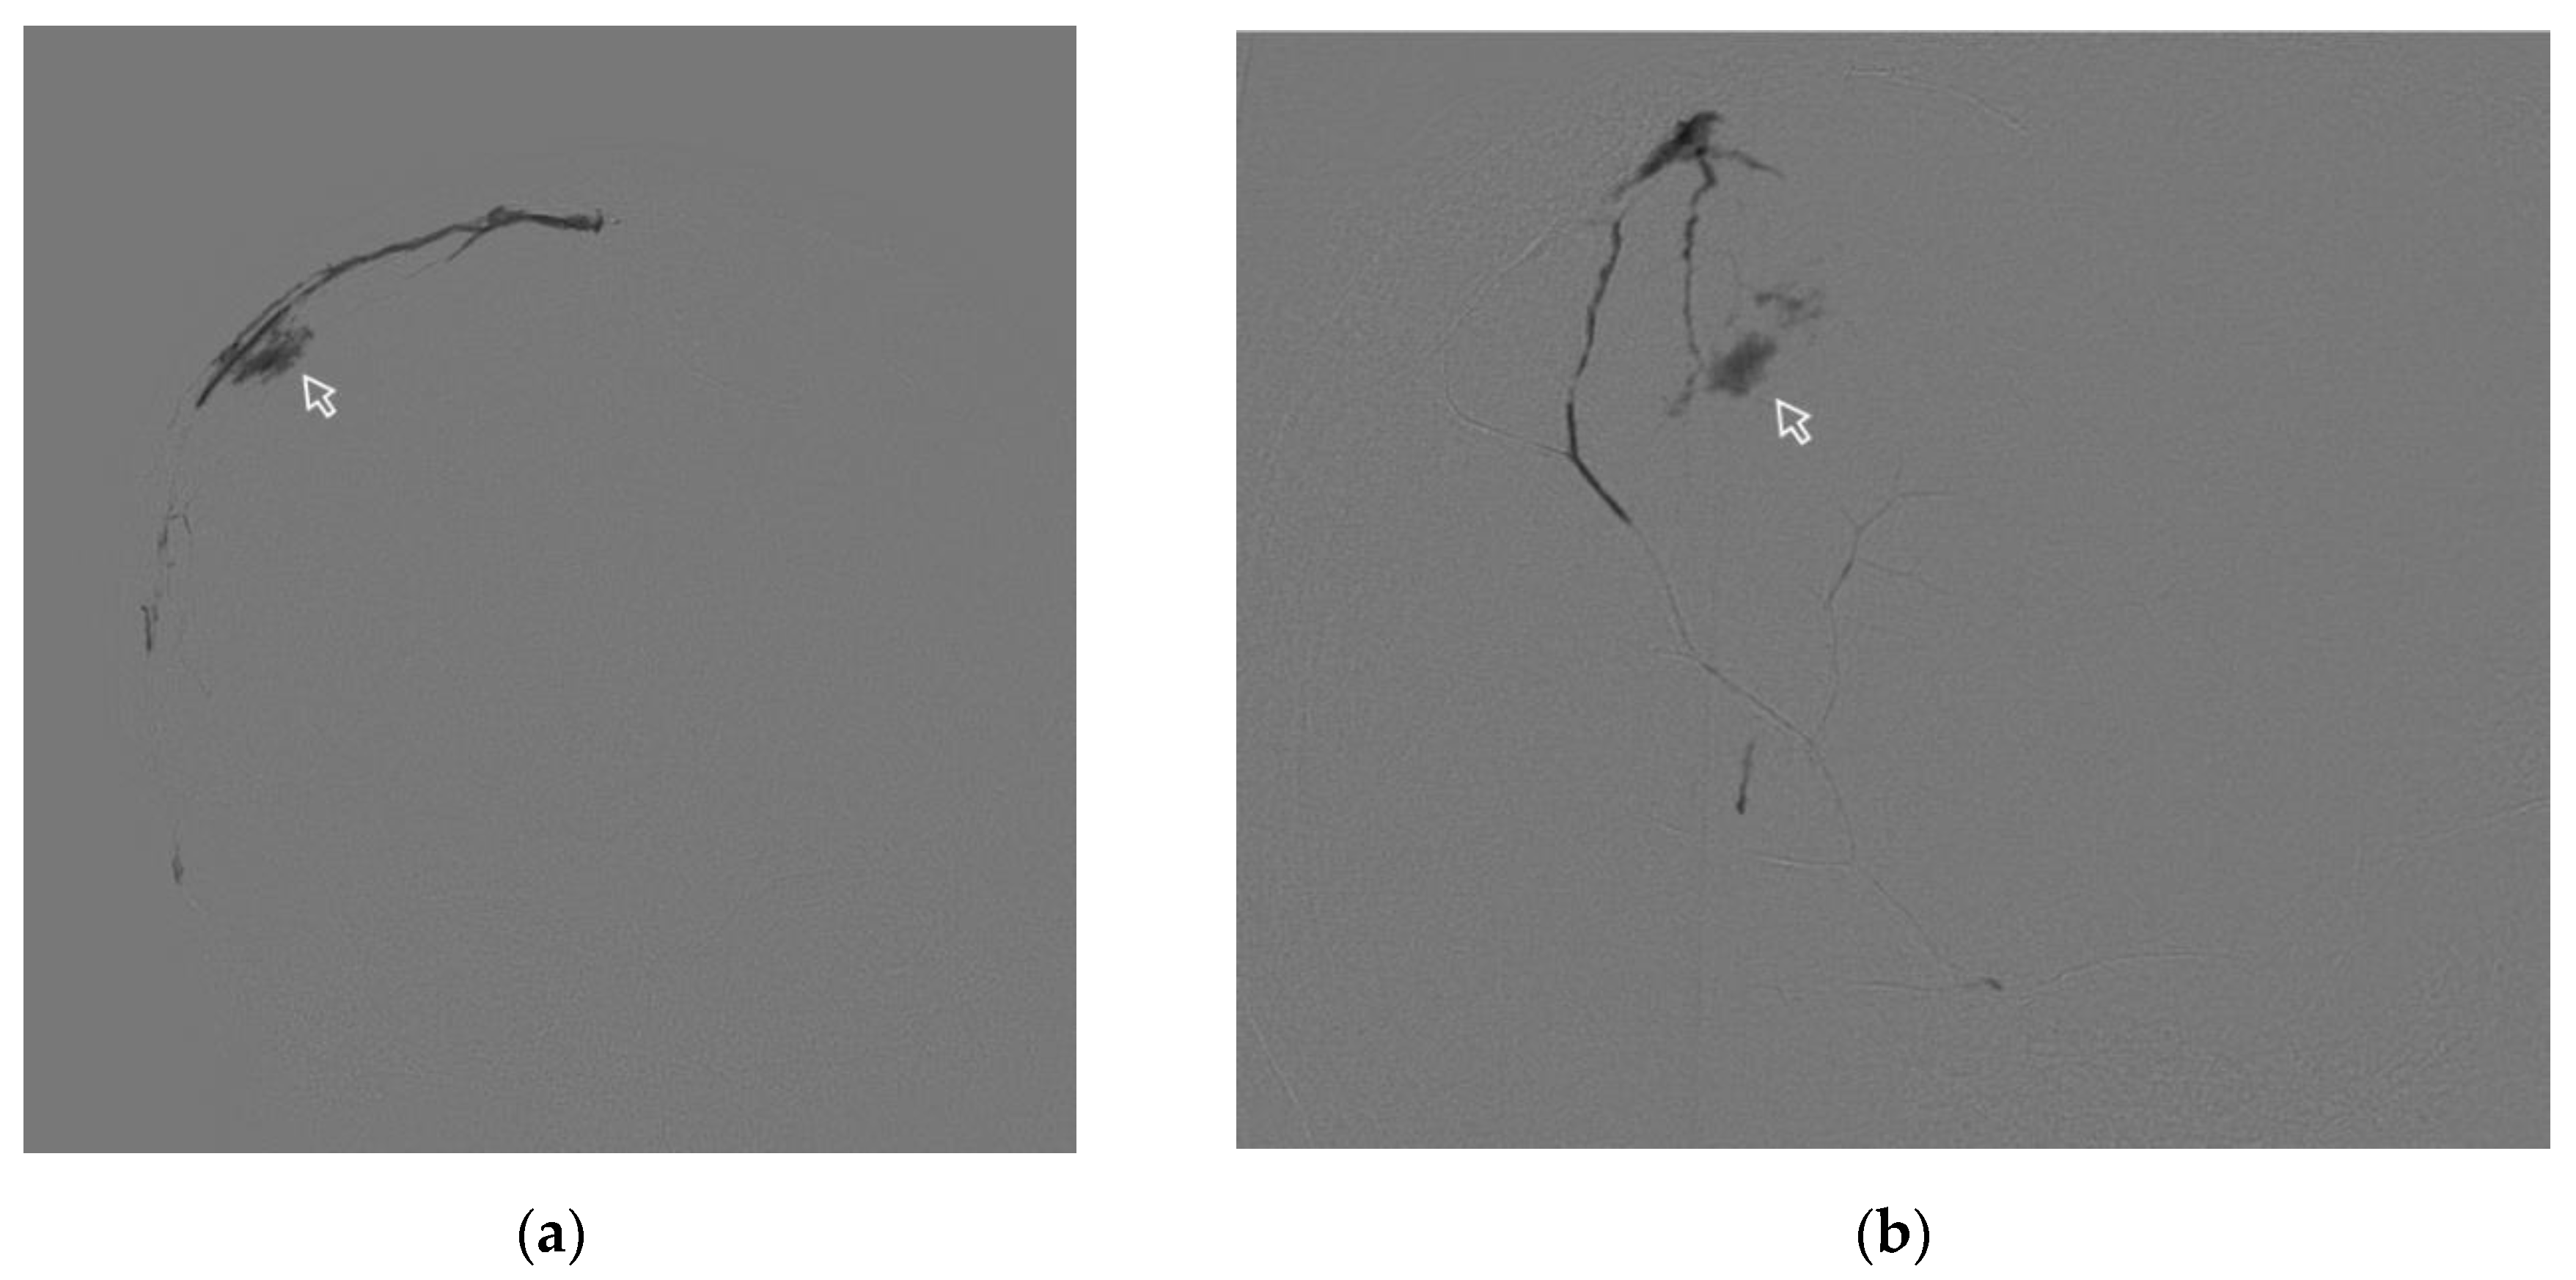

3.4.2. Case #2

A 63-year-old man, with a history of head trauma, came to the clinic with complaints of headaches. mRS at the time of admission 1. CT scan of the brain showed a right-sided chronic subdural haematoma with a maximum thickness of 13 mm. Midline shift of 3 mm. During embolization of the right MMA by ONYX 18, there was extravasation of the gel-like composition on 9.4 min. Extravasation did not lead to clinically significant complications but prevented further embolization. (Figure 9).

Figure 9. Posterior-anterior (a) and lateral (b) DSA images show the process of spreading NAGLEM (ONYX 18) along the branches of the right MMA. The white frame arrows indicate extrvasation of the embolic agent (ONYX 18).